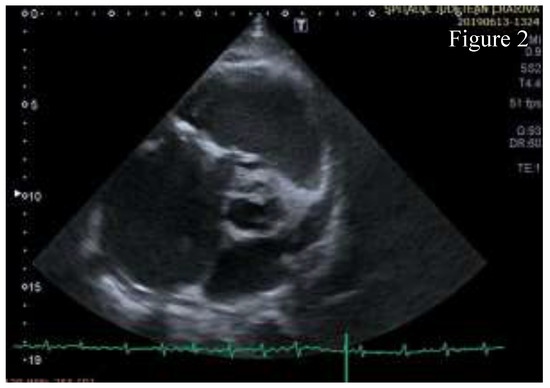

How Rare Is Isolated Rheumatic Tricuspid Valve Disease?

by Edme R. Mustafa, Octavian Istrătoaie, Roxana Mandia, Georgică C. Târtea and Cristina Florescu

J. Mind Med. Sci. 2020, 7(1), 128-132; https://doi.org/10.22543/7674.71.P128132 - 20 Apr 2020

The incidence of rheumatic fever (RF) has markedly decreased in Europe since the beginning of the 20th century due to improved living conditions, early antibiotic therapy in streptococcal pharyngitis, and changes in serotypes of circulating streptococci. Isolated outbreaks of RF are still found in various parts of the world and the disease has changed its presentation with milder joint symptoms and subclinical carditis that make the correct diagnosis more difficult. Patients can present many years later with severe valve disease and significant disability. This article presents a case of isolated rheumatic tricuspid valve disease that presented with signs and symptoms of right heart failure and severe valve damage. Isolated involvement of the tricuspid valve is rarely found in rheumatic fever and a thorough differential diagnosis is needed. Full article

Show Figures

Figure 1